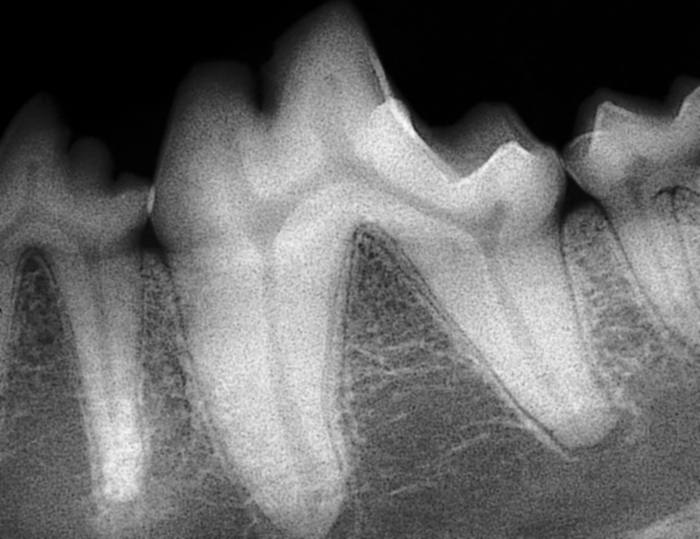

Radiograph of normal periodontium

Gingivitis only, due to plaque deposition and lack of home care. Reversible by diligent homecare or professional scaling and polishing. There is no attachment loss at this stage. Without treatment and with an increase in quantity or virulence of bacteria, this will lead to stage 2.